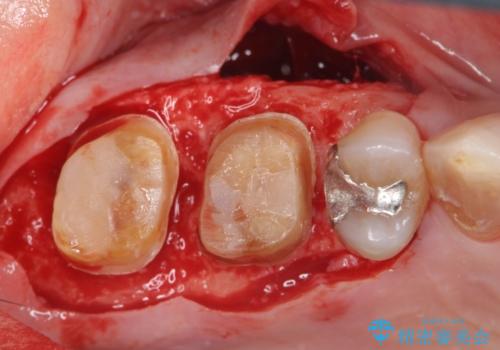

歯周ポケットの除去と再補綴治療

歯周ポケットの除去を歯周外科により行ったのち精度が高く清掃のしやすいセラミック治療による再補綴を行います。

歯周病は痛みのないまま進行し、最終的に歯が抜けてしまう病気です。

歯を残せるうちに歯周ポケットの除去を行い歯の予後を良くすることができます。